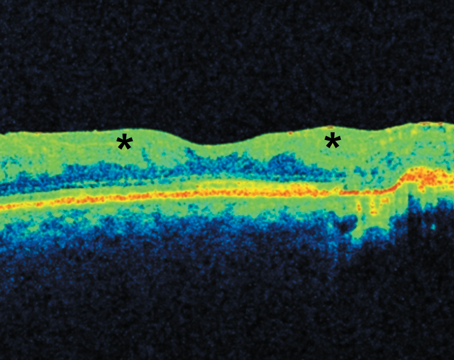

Optical coherence tomography in the management of diabetic retinopathy

Tips on what to look for when using this technology to assess and follow patients with DR.